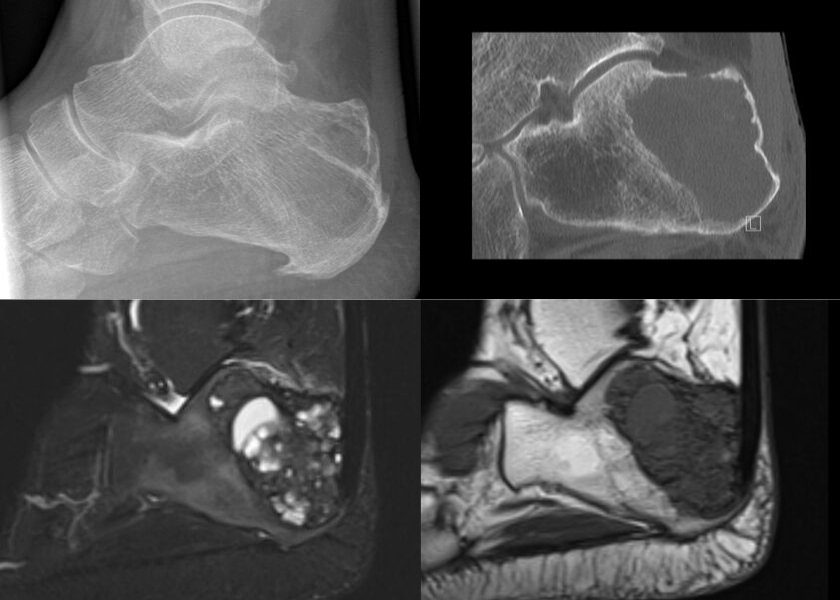

Die Diagnostische und Interventionelle Radiologie bietet alle gängigen und speziellen Untersuchungstechniken an neusten Geräten an. Dazu gehören unter anderem die Sonographie, das konventionelle Röntgen, die Computertomographie (drei 128-Zeilen-Geräte der neusten Generation) sowie die Magnetresonanztomographie (zwei 1,5-Tesla-Geräte sowie ein 3-Tesla-Gerät der neusten Generation). In zwei hochmodernen Hybrid-OPs ist zum Beispiel die endovaskuläre Diagnostik von gutartigen Weichgewebstumoren möglich.

Gutartiger, sogenannter „Brauner Tumor“ im Fersenbein

Neben den rein bildgebenden Verfahren werden am Institut für Diagnostische und Interventionelle Radiologie auch minimal-invasive Therapien durchgeführt. Dazu gehören unter anderem CT-gestützte Interventionen (zum Beispiel Entnahmen von Gewebeproben oder Radiofrequenzablationen von Osteoidosteomen) oder endovaskuläre Interventionen (zum Beispiel Embolisationen von Hämangiomen). In Kooperation mit der Nuklearmedizin werden auch die PET/CT und die Skelettszintigraphie angeboten.